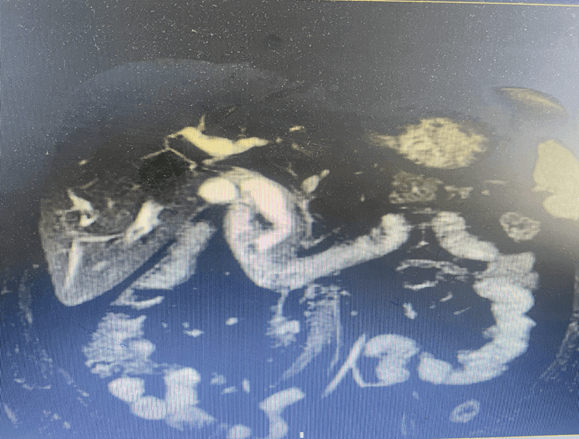

该技术充分利用胆囊管这一天然通道。手术中,医生在腹腔镜下,将纤细的胆道镜经胆囊管插入胆总管,如同配备高清探头的“精工镊子”,在直视下精准定位结石,并利用网篮等器械将其完整取出。